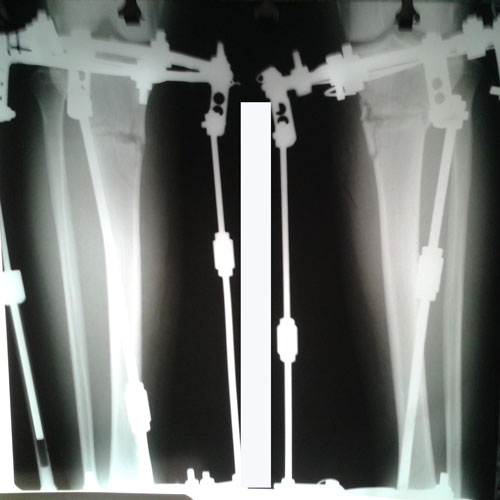

РЕНТГЕН ДО ОПЕРАЦИИ

Рентген на стадии коррекции